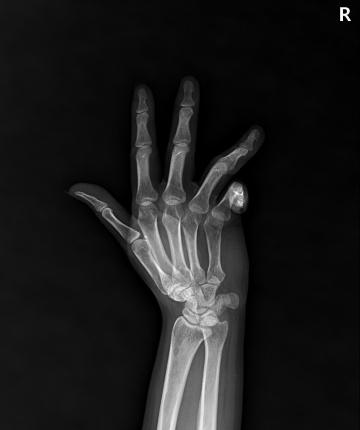

수술전

2022.04.29

수술후

2023.01.04